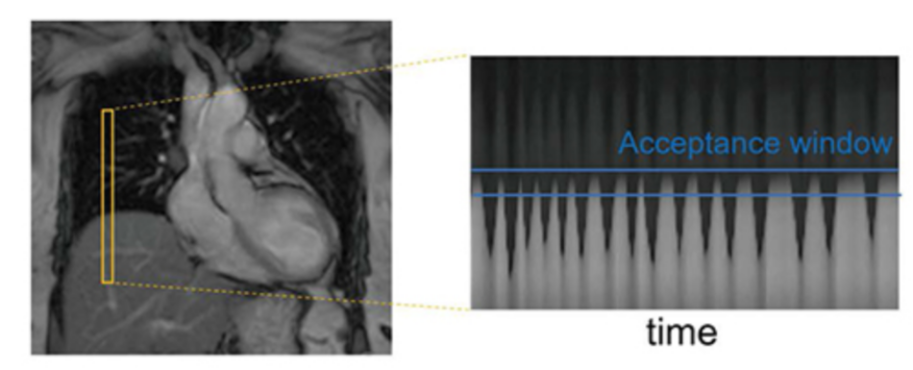

A “pencil‑beam” excitation creates a narrow, cylindrical region of magnetization. By positioning this small beam over the liver you get a continuous signal that changes as the patient breathes: the liver moves with respiration, and that motion modifies the measured signal. This motion signal is used as a respiratory trace to accept data only during a chosen breathing phase (for example, end‑expiration) and to reject data acquired at other times, reducing motion artifacts in cardiac MRI.